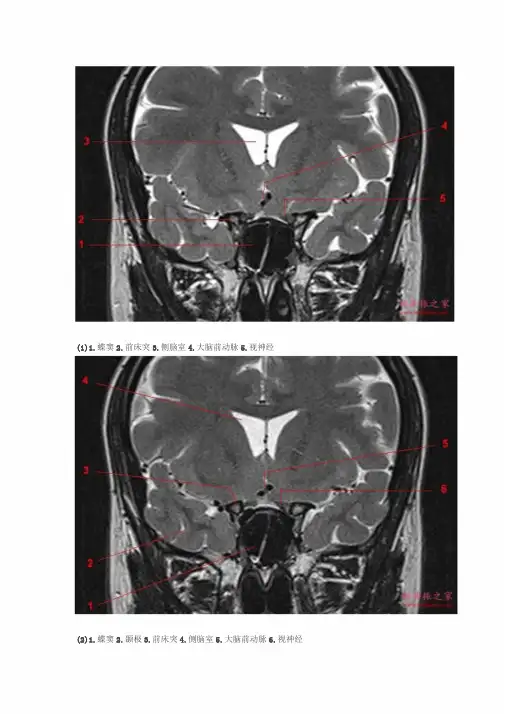

(1)1.蝶窦2.前床突3.侧脑室4.大脑前动脉5.视神经

(2)1.蝶窦2.颞极3.前床突4.侧脑室5.大脑前动脉6.视神经